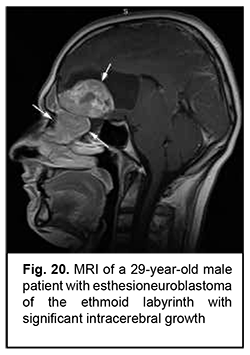

Esthesioneuroblastoma is a tumor that originates from the olfactory epithelium in the superior nasal meatus and grows invasively (Fig. 20). It is located close to the lamina cribrosa, which causes its further intracranial and intracerebral extension. Patients with esthesioneuroblastoma tend to have better survival rates than those with malignant epithelial ASBOT due to radical surgery and effective combination therapy of cancer.